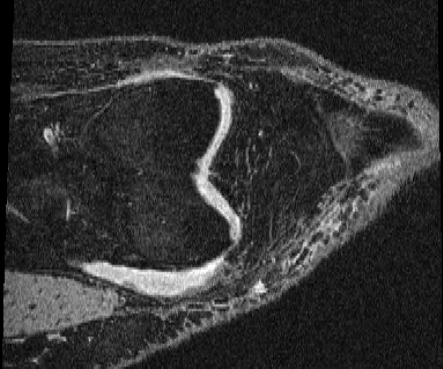

HCP Brain MRI We train on 1076 brain-extracted T1w images from the HCP dataset [24] and test on a sample of 100 pairs between 36 images via mean Dice over 28 midbrain structures [20, 21]. We train and execute the network at [130155130], then compute the Dice score at full resolution.

OASIS Brain MRI We use the OASIS-1 [12] data preprocessed by [9]. This dataset contains images of 414 subjects. Following the data split in [14], we train on 255 images and test on 153 images555Due to changes in the OASIS-1 data, our test set slightly differs from [14]. We evaluate all methods using our testing protocol so that results are consistent.The images in the dataset are of size [160192224], and we crop the center of the image according to the preprocessing in [14], leading to a size of [160144192]. During training, we sample image pairs randomly from the train set. For evaluation, we randomly pick 5 cases as the fixed images and register all the remaining 148 cases to the 5 cases, resulting in 740 image pairs overall.

| Moving Image | Warped Image | Fixed Image | Moving Image | Warped Image | Fixed Image |